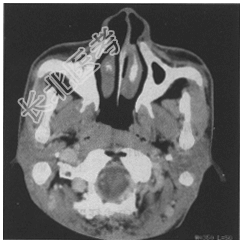

- [材料题] 患者,男,48岁。主诉为鼻塞、头痛3个月余,3个月前始出现鼻塞、流涕,偶有涕中带血,并伴有头痛,呈阵发性,既往体健,否认高血压、心脏病病史。实验室检查未见明显异常。

- 简答题2、患者所做检查如图,请问你诊断为何种疾病?

- 简答题3、参考CT图像你的诊断依据是什么?